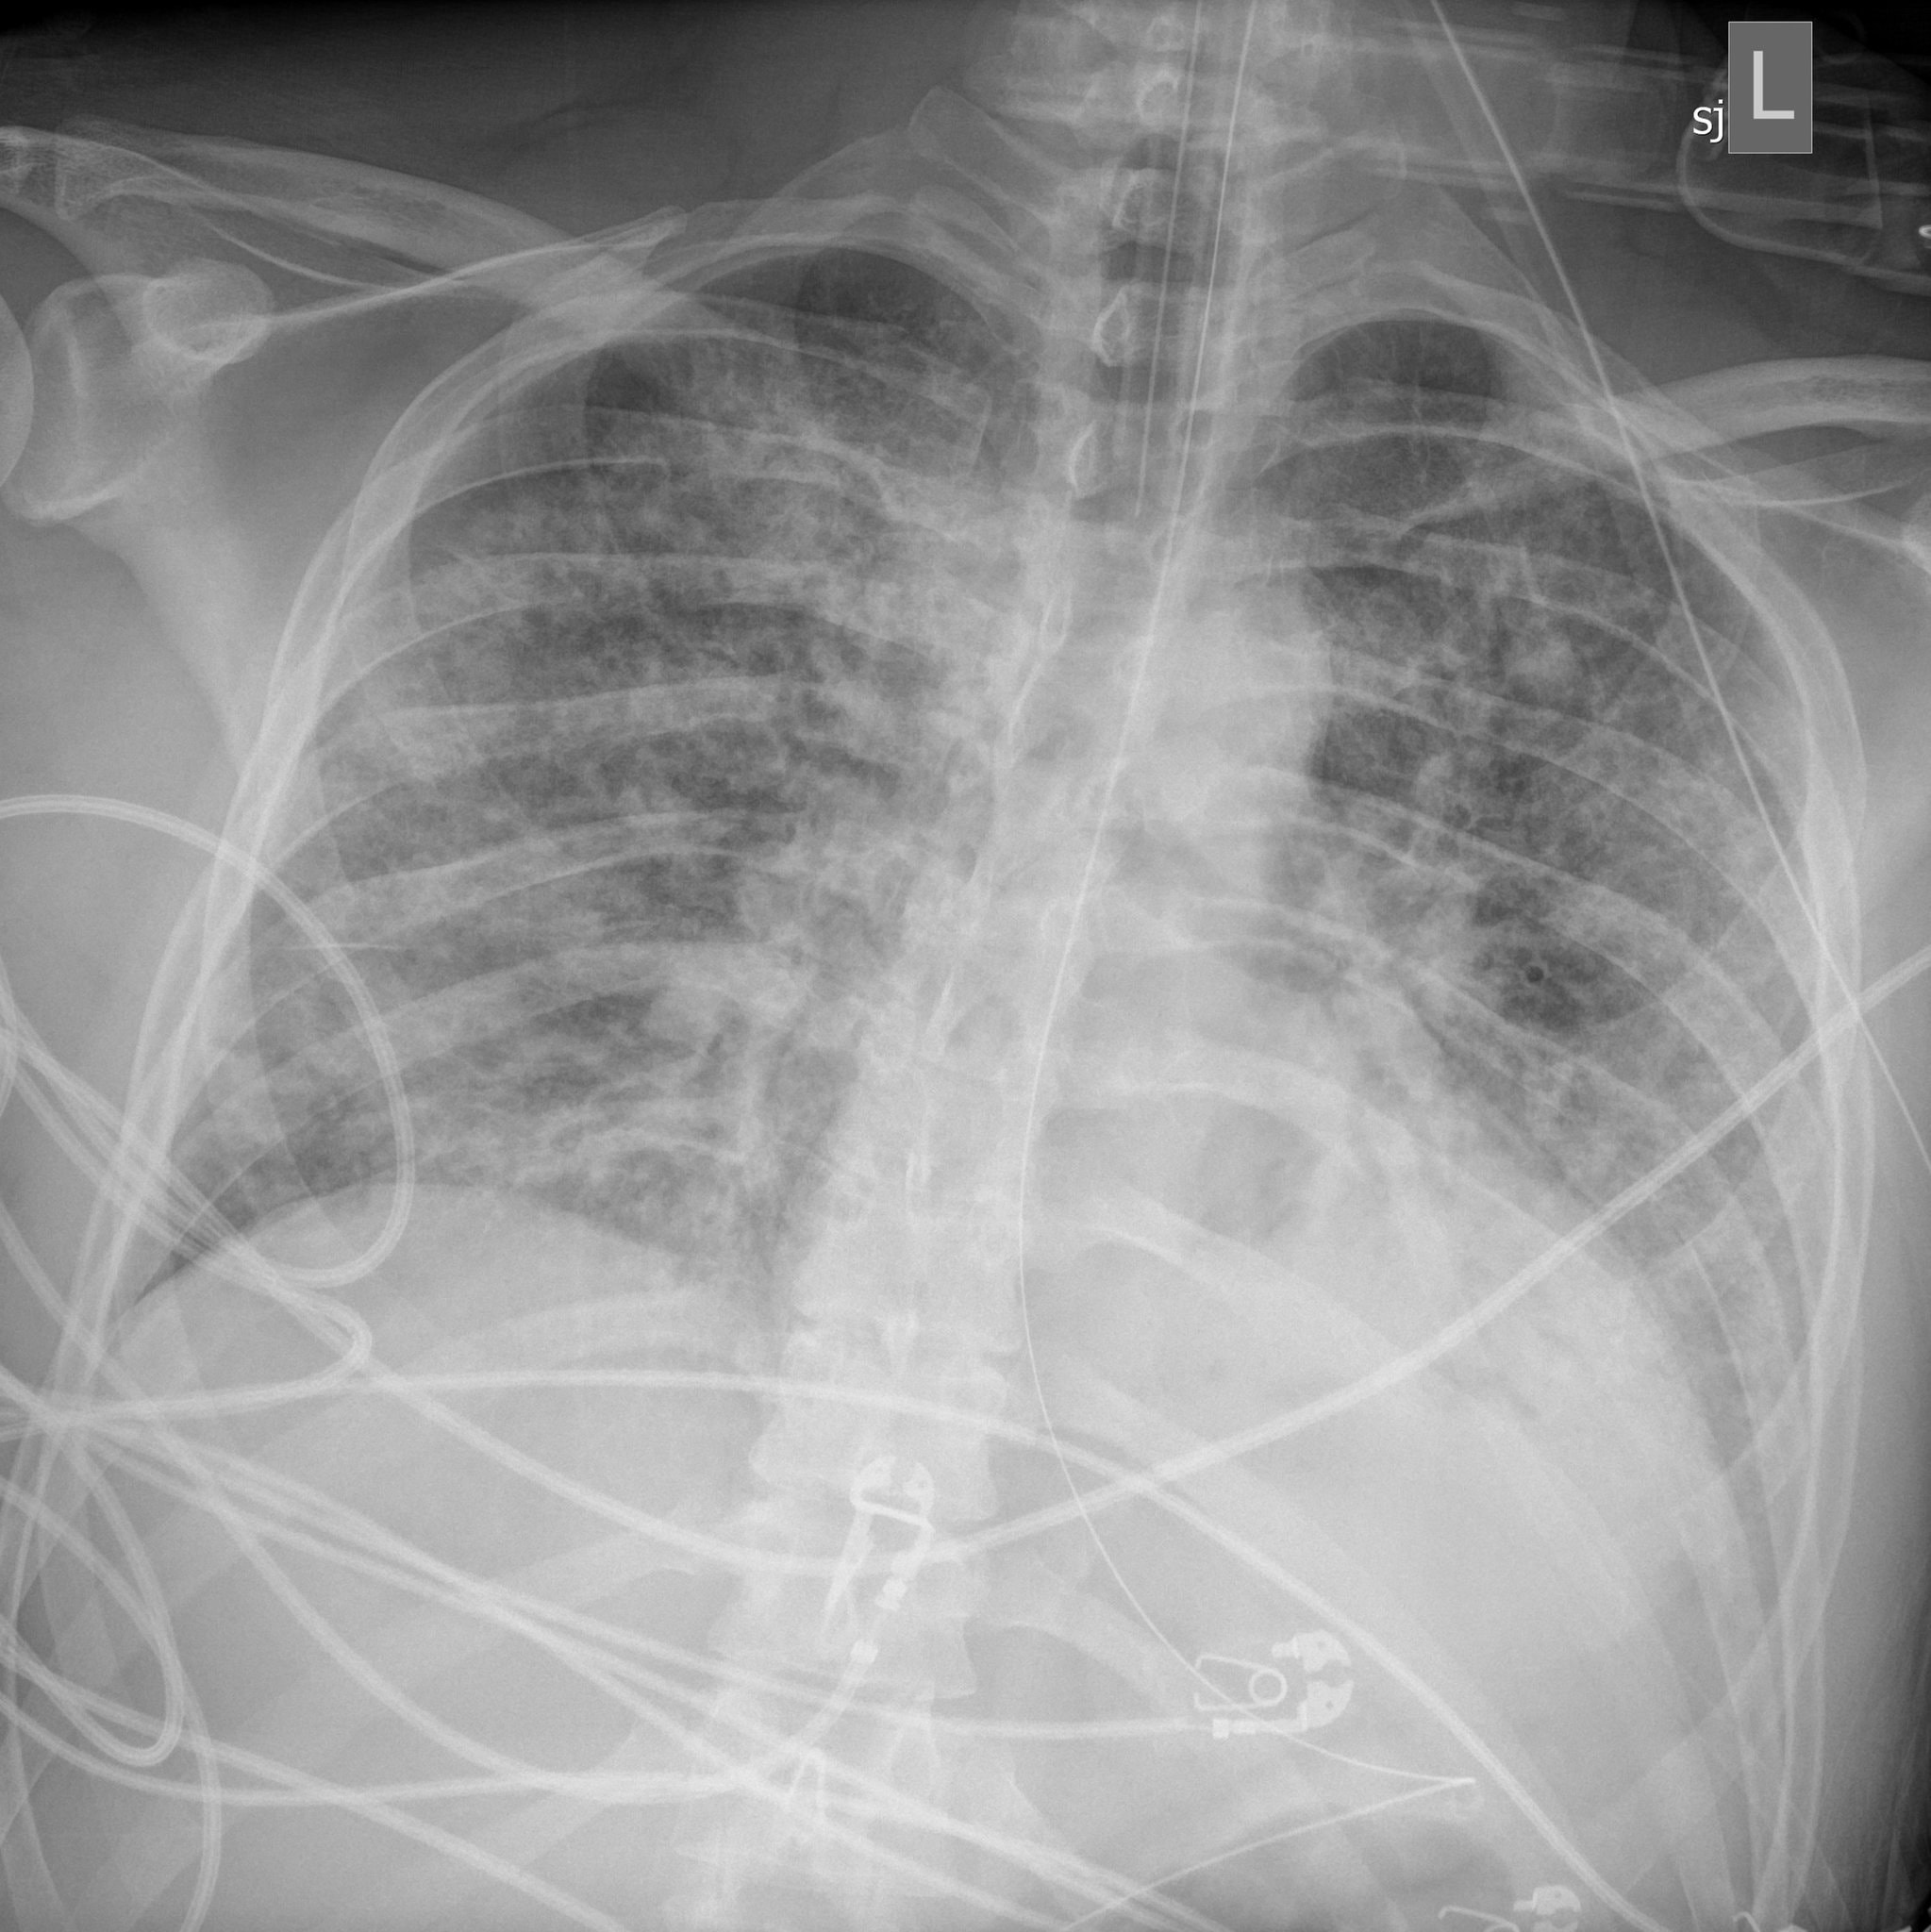

Khi được đưa đến bệnh viện, tình trạng sức khỏe của Jim khiến các bác sĩ vô cùng quan ngại. X-quang phổi của anh lúc đó cho thấy cơ quan này đang bị nghẹt ứ nghiêm trọng.

"Đó là một trong những tấm X-quang tệ nhất tôi từng thấy", bác sĩ Paul Currier - thành viên tổ điều trị - nói.

Hình ảnh X-quang phổi của Jim Bello có nhiều mảng trắng đục, cho thấy cơ quan này đang bị nghẽn dịch và không đủ chỗ cho không khí lưu thông. Ảnh: Massachusetts General Hospital.

Kỳ tích đã xảy ra. Vài ngày sau đó, phần trắng đục trên ảnh chụp X-quang phổi của Jim đã thuyên giảm. Jim Bello từng bước cai ECMO, phản ứng tốt với các yêu cầu của bác sĩ dù vẫn phải sử dụng máy thở thường.